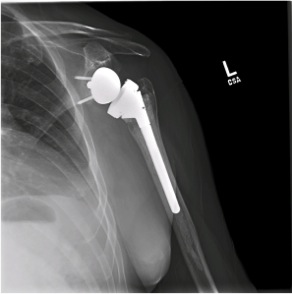

Shoulders Replacement

What is Shoulders Replacement?